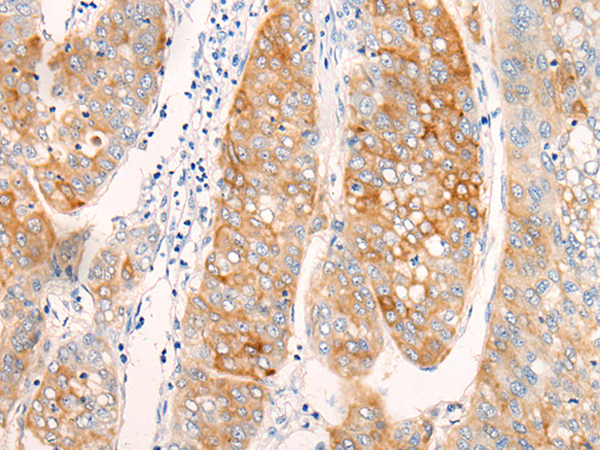

抗 原: AIFM2

ELISA, IHC |

IHC positive control: |

Human liver cancer |

IHC Recommend dilution: |

20-100 |